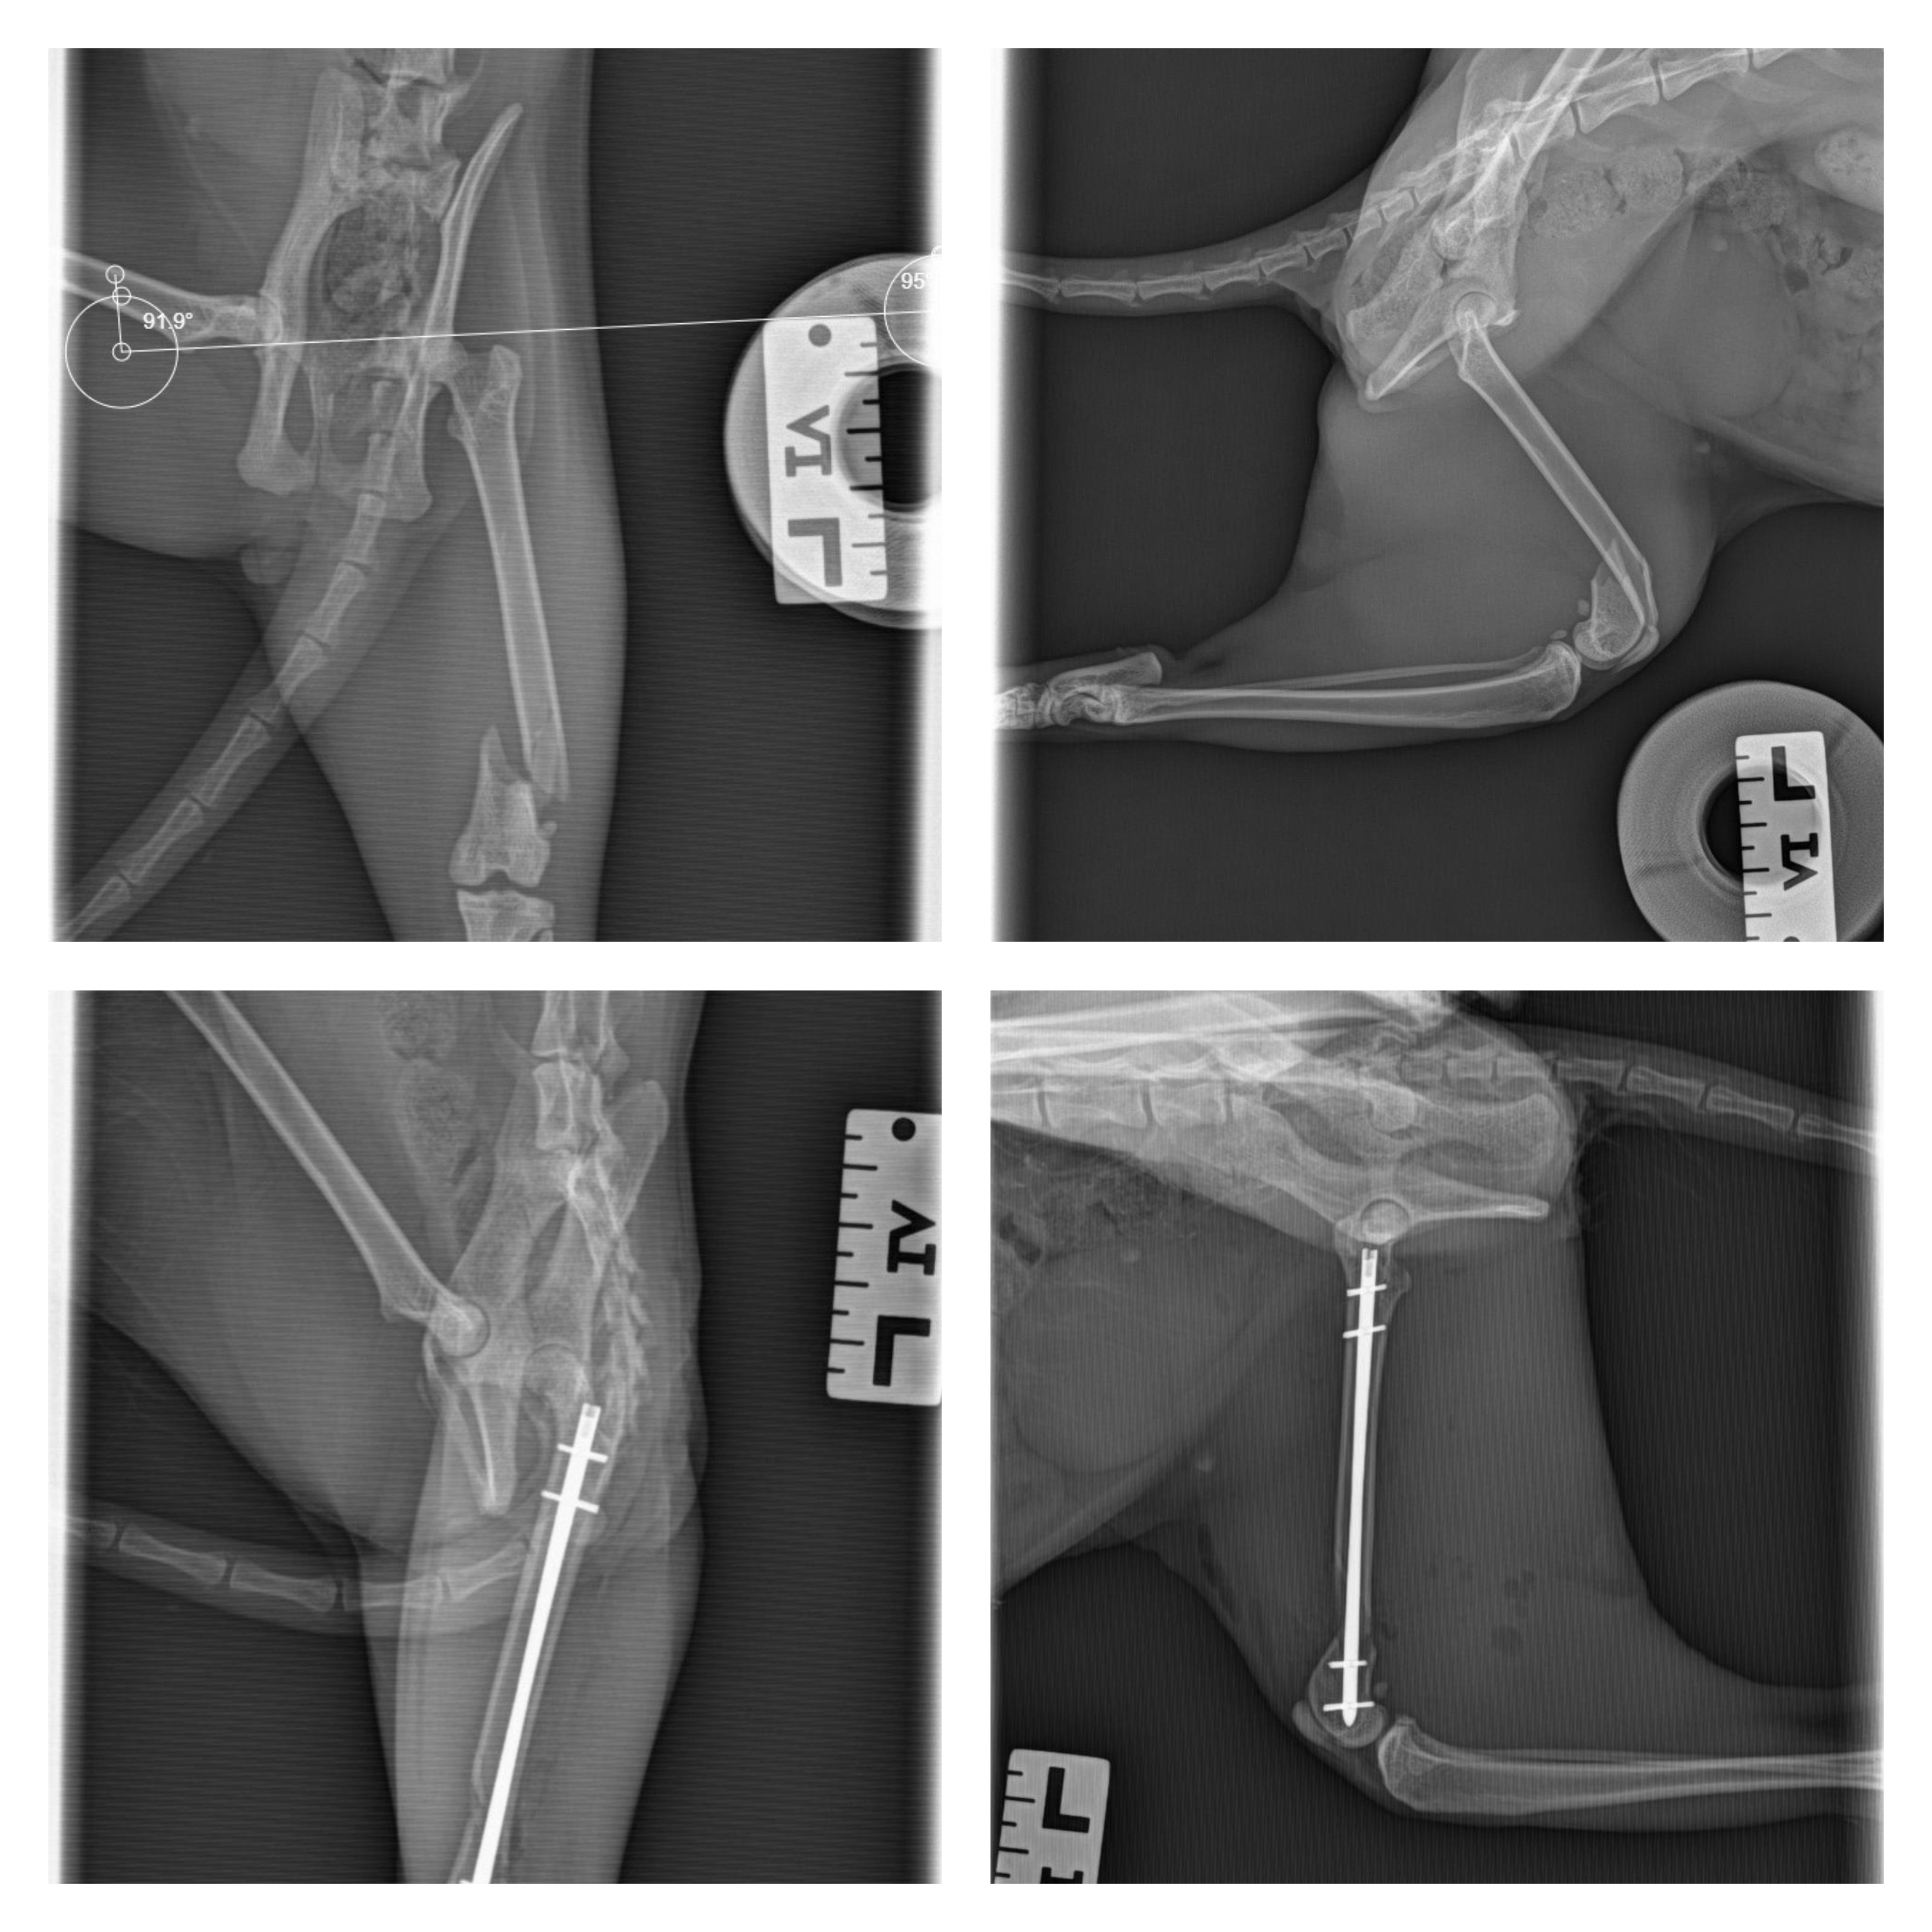

La méthode I-LOC (Intra-médullary Locking Osteosynthesis) est une technique innovante de fixation des fractures. Elle consiste à insérer une broche intra-médullaire verrouillée par des vis, offrant ainsi une stabilité optimale tout en minimisant les traumatismes sur les tissus environnants.

Lors de l’opération, l’implant a été placé avec précision pour aligner parfaitement les fragments osseux. Cette stabilité a permis de favoriser une réparation rapide et efficace.